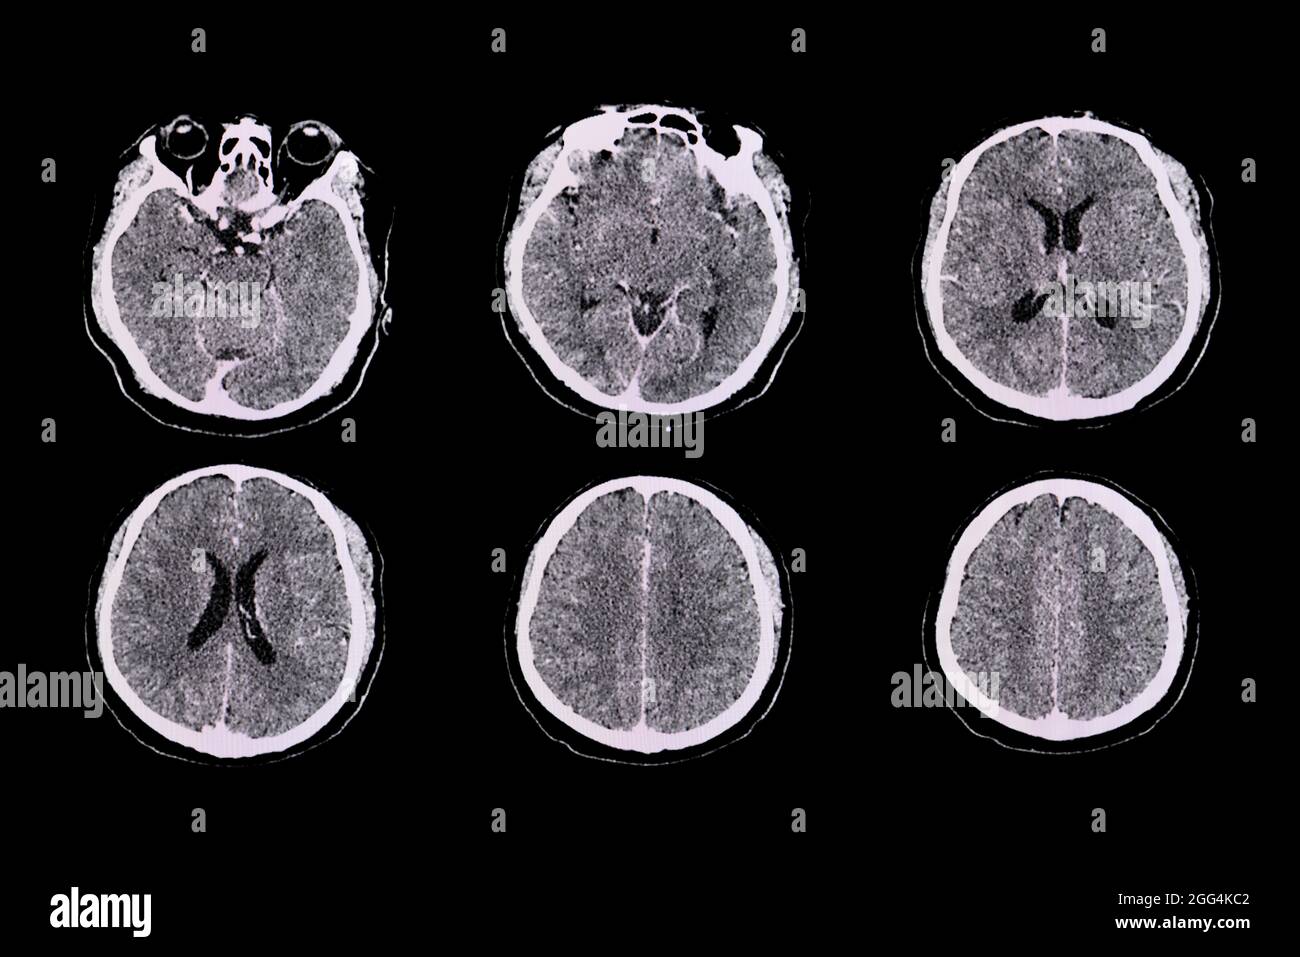

Scanner du cerveau d'un patient atteint d'une méningite à Streptococcus suis présentant une amélioration leptomeningeal le long des sulci corticaux pariétaux bilatéraux. Banque D'Imageshttps://www.alamyimages.fr/image-license-details/?v=1https://www.alamyimages.fr/scanner-du-cerveau-d-un-patient-atteint-d-une-meningite-a-streptococcus-suis-presentant-une-amelioration-leptomeningeal-le-long-des-sulci-corticaux-parietaux-bilateraux-image440196738.html

Scanner du cerveau d'un patient atteint d'une méningite à Streptococcus suis présentant une amélioration leptomeningeal le long des sulci corticaux pariétaux bilatéraux. Banque D'Imageshttps://www.alamyimages.fr/image-license-details/?v=1https://www.alamyimages.fr/scanner-du-cerveau-d-un-patient-atteint-d-une-meningite-a-streptococcus-suis-presentant-une-amelioration-leptomeningeal-le-long-des-sulci-corticaux-parietaux-bilateraux-image440196738.htmlRF2GG4KC2–Scanner du cerveau d'un patient atteint d'une méningite à Streptococcus suis présentant une amélioration leptomeningeal le long des sulci corticaux pariétaux bilatéraux.